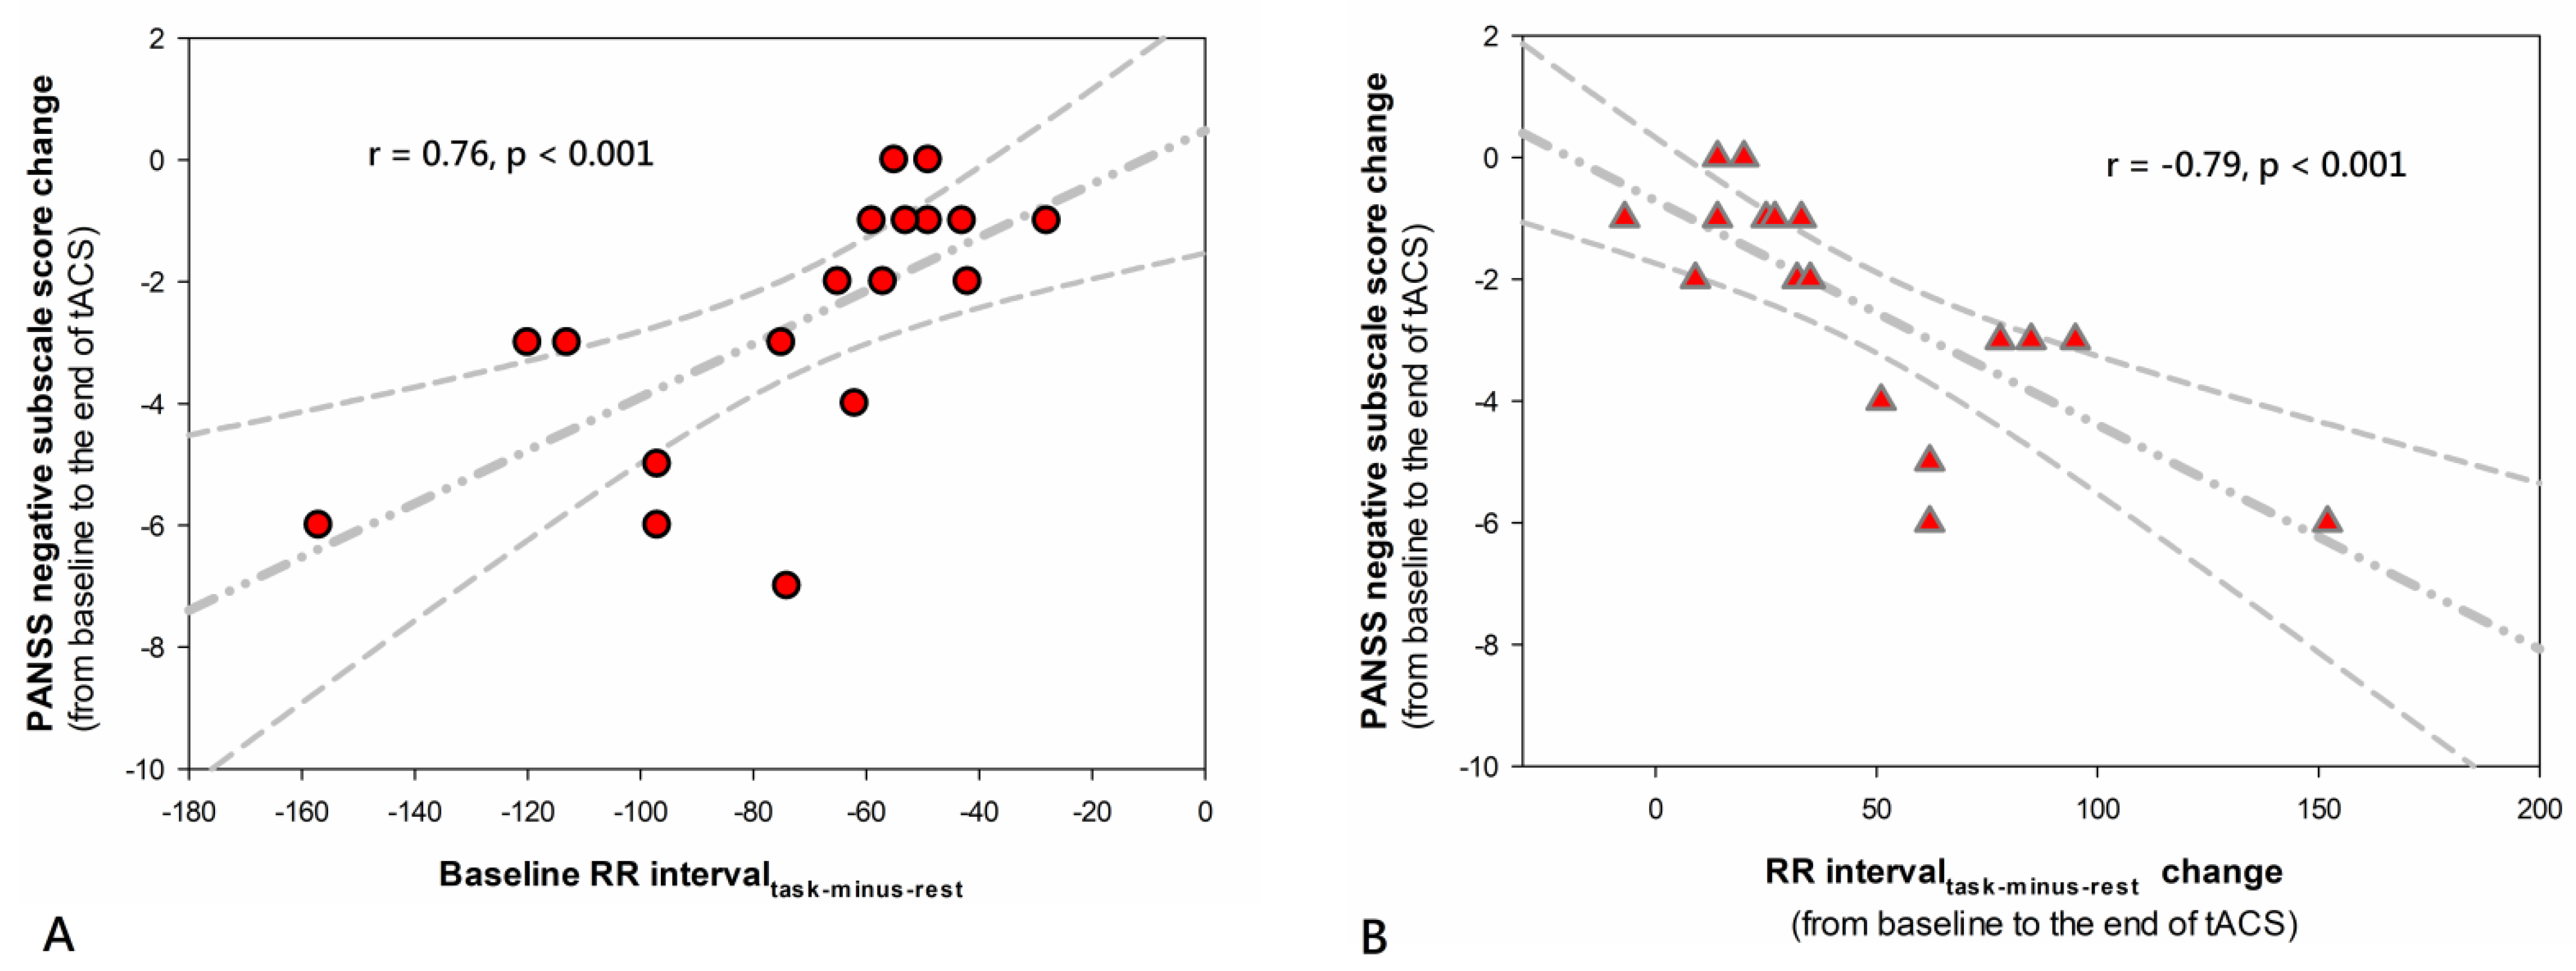

3.5. Biologic Marker